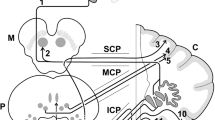

The spatially unbiased atlas template (SUIT) is a spatially unbiased, high-resolution atlas template of the human cerebellum and brainstem, which maintains the anatomical detail of the cerebellar structures [12]. Our goal was to perform a detailed study of cerebellar morphology in HD, using the SUIT toolbox, and, secondarily, to perform a clinical-anatomical correlation.

VBM-SUIT Tool

The images were divided into patients and controls. Each subject was treated at the voxel-by-voxel level. The 3D–MRI images acquired in DICOM format were transformed to NIfTI (DCM2Nii software: http://www.mccauslandcenter.sc.edu/mricro/mricron/dcm2nii.html). In order to minimize any error, the images were aligned along the anterior commissure and rotated in sagittal, coronal, and axial planes. We used the SUIT tool (version 3.2), which isolates the infratentorial structures from surrounding tissue and generates targeted maps (gray matter (GM), white matter, and cerebrospinal fluid), providing a more accurate alignment between subjects than “whole-brain” methods (http://www.icn.ucl.ac.uk/motorcontrol/imaging/suit.htm). The SUIT tool classifies the cerebellar lobules more precisely than other VBM techniques [15,16,17]. The segmented GM images were normalized to the SUIT template. Then, we repositioned the generated maps to correct the variation of induced spatial normalization volume. Next, we conducted homogeneity tests using the images’ covariance. Finally, the images were smoothed by a Gaussian filter kernel with 3 mm full-width half maximum (FWHM) contained in SPM12/Dartel (http://www.fil.ion.ucl.ac.uk) to satisfy the normal distribution assumed for statistical analysis of regional differences. The generated statistical parametric map identifies regions with significant differences in cerebellum.